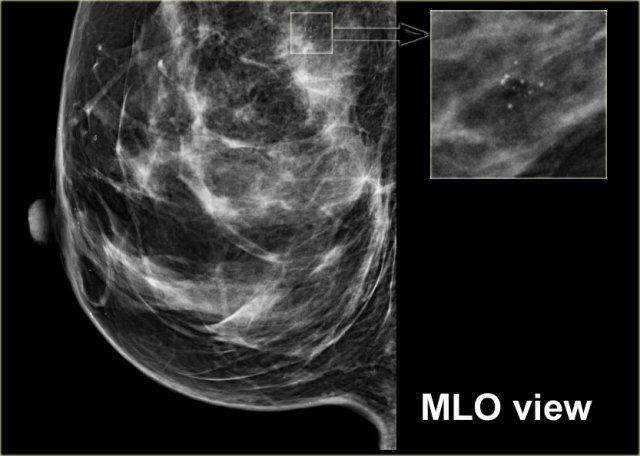

Đây là một ví dụ khác về dấu hiệu hình xăm.

Trước tiên hãy chú ý rằng có một số vôi hóa rõ ràng nằm trong da (mũi tên).

Cụm vôi hóa trên tư thế MLO có cấu hình hoàn toàn giống với cụm trên tư thế CC (hình tiếp theo).

Trên tư thế CC, cấu hình của các vi vôi hóa hoàn toàn giống nhau.

Nếu các vôi hóa này nằm ở trung tâm vú, chúng phải có cấu hình khác nhau vì góc chiếu khác nhau.

Chỉ khi vôi hóa nằm trong da thì cấu hình của chúng mới giữ nguyên.